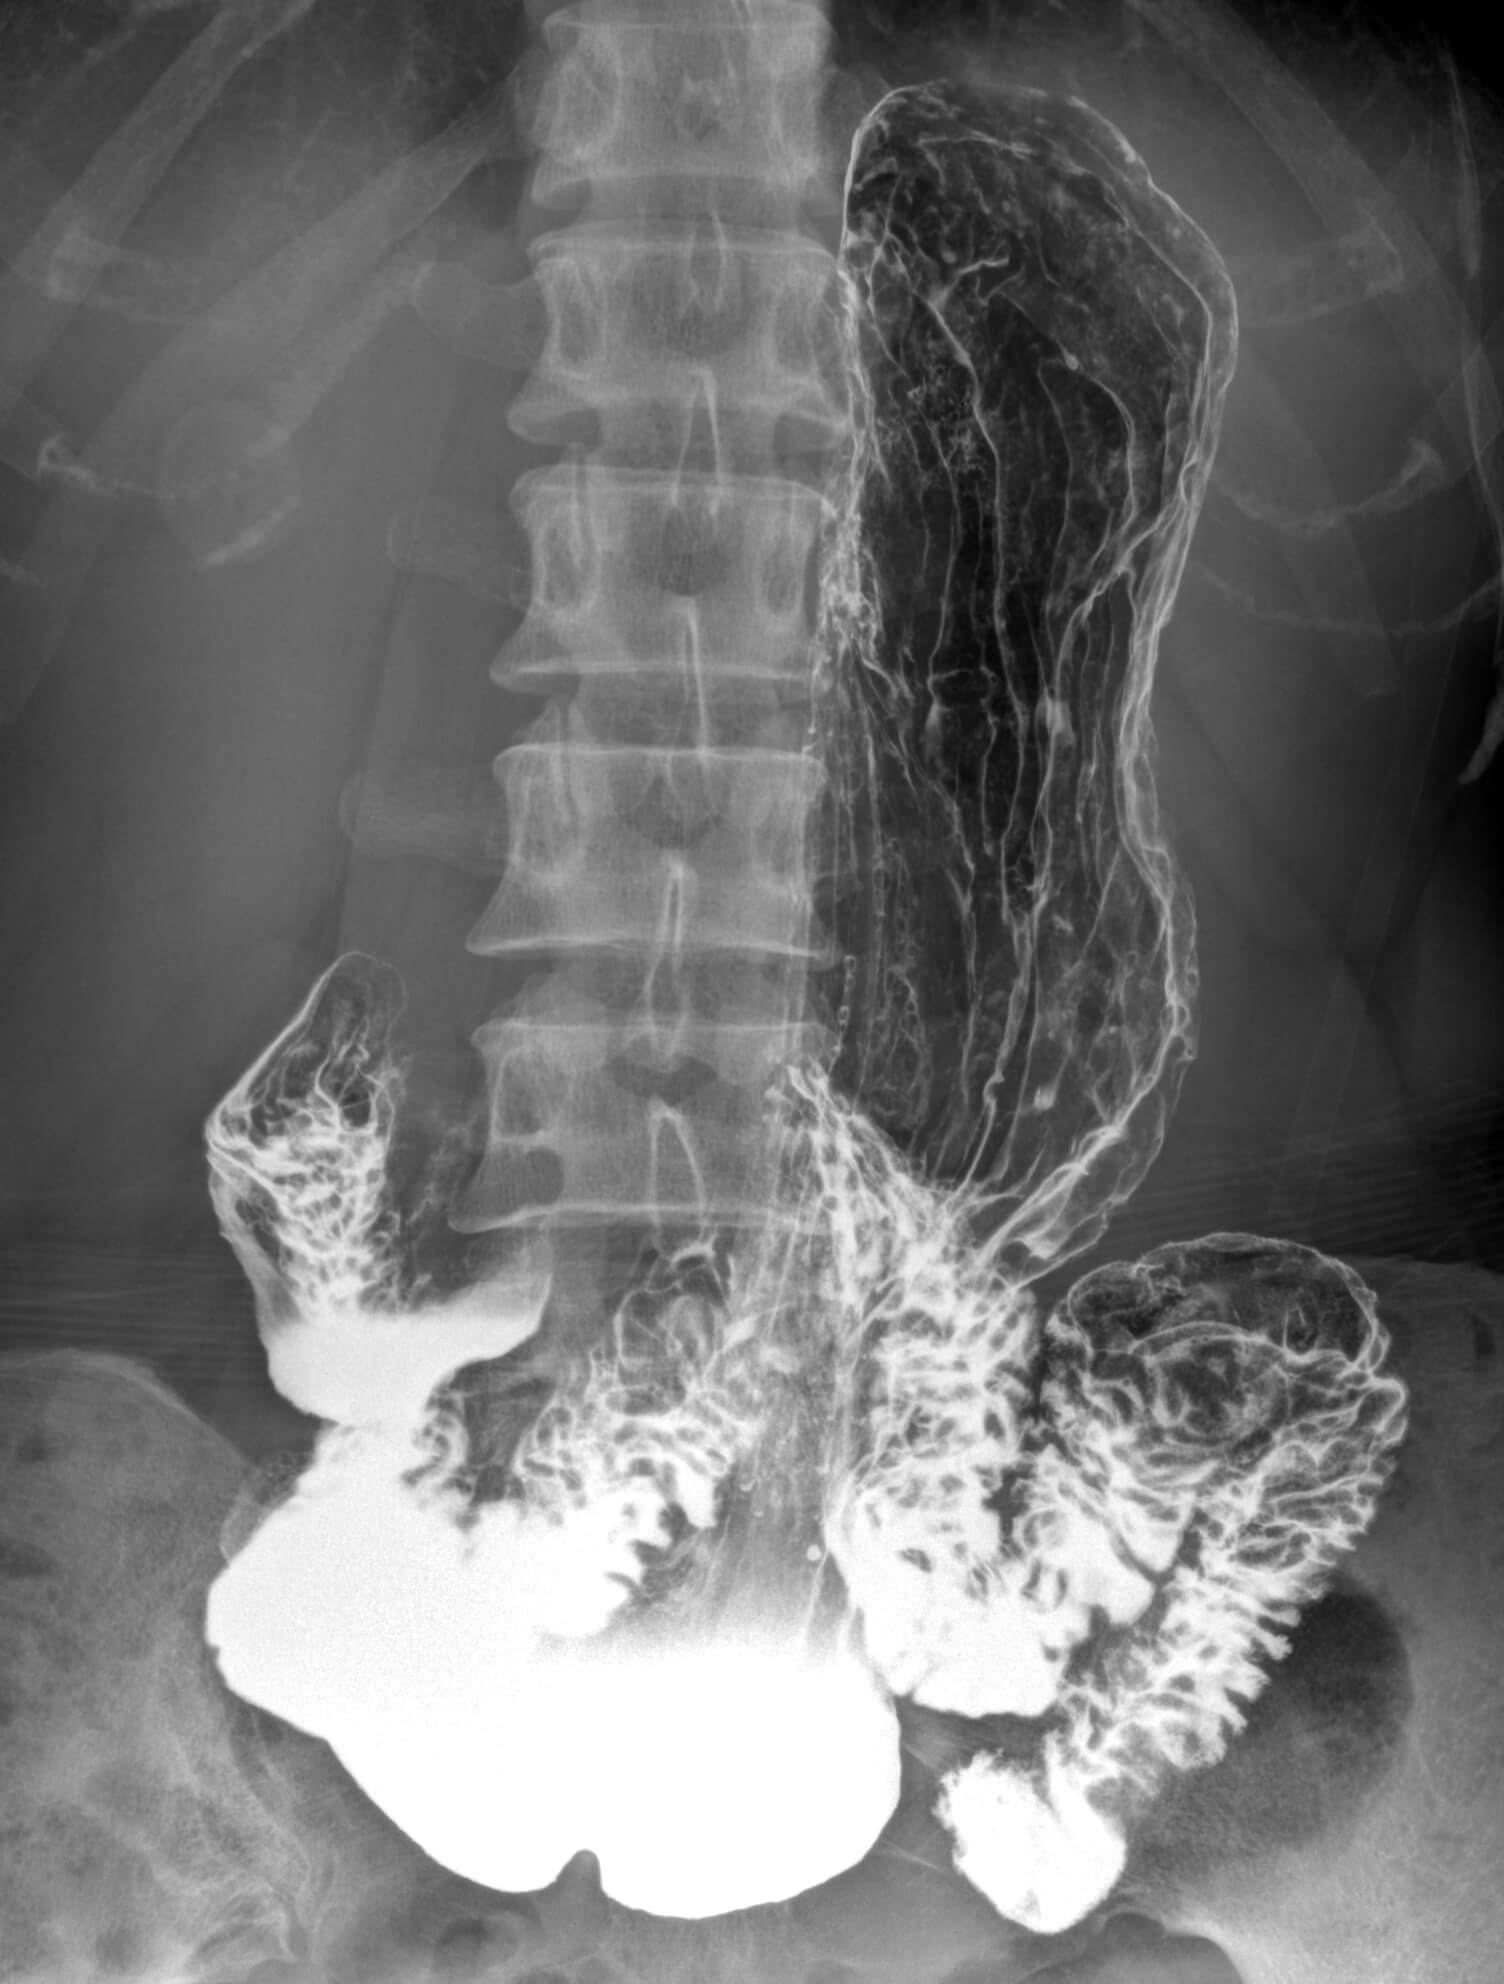

• Wide clinic applications

• Clever post processing of fluoroscopic image